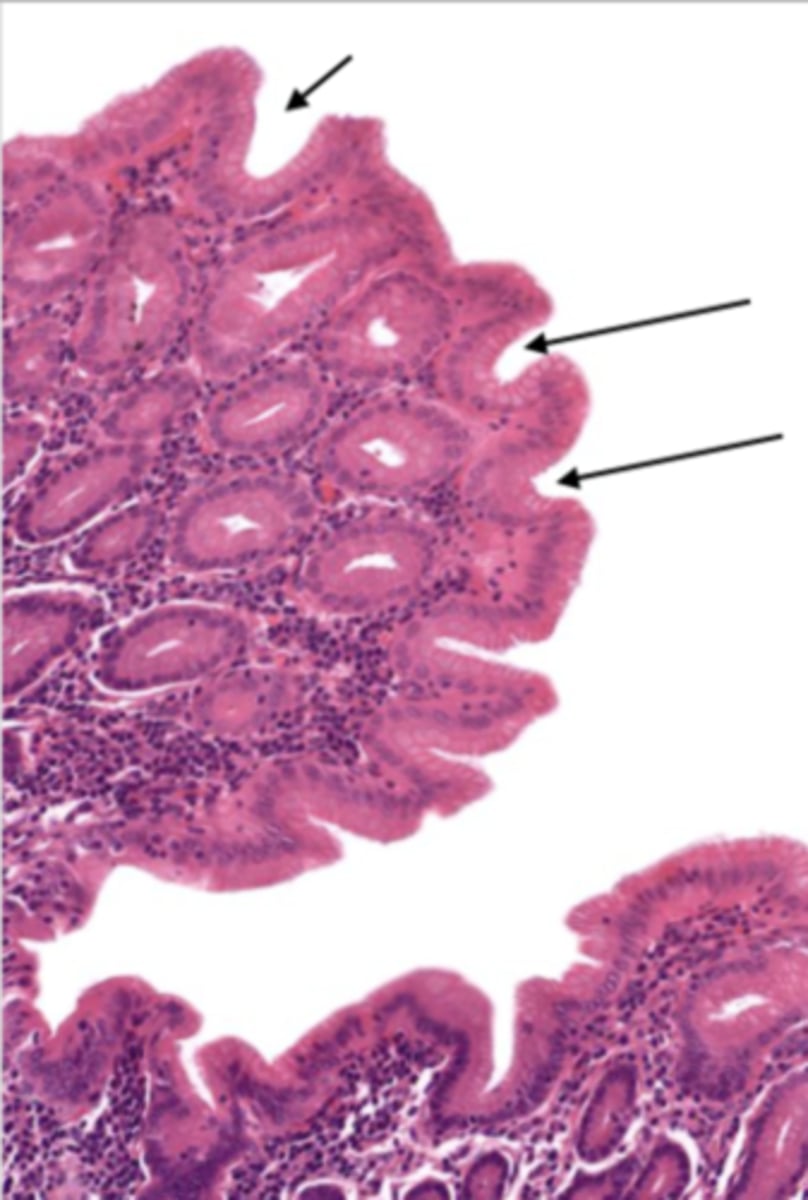

gallbladder (histology)

gallbladder

this tissue's wall structures/layers are different than the rest of the organs

simple columnar epithelium

lumen (gallbladder)

mucosa (gallbladder)

mucosal epithelium (gallbladder)

lamina propria (gallbladder)

muscularis mucosa and submucosa

gallbladder tissue does not have _______ and ______

muscularis externa (gallbladder)

serosa/adventitia (gallbladder)